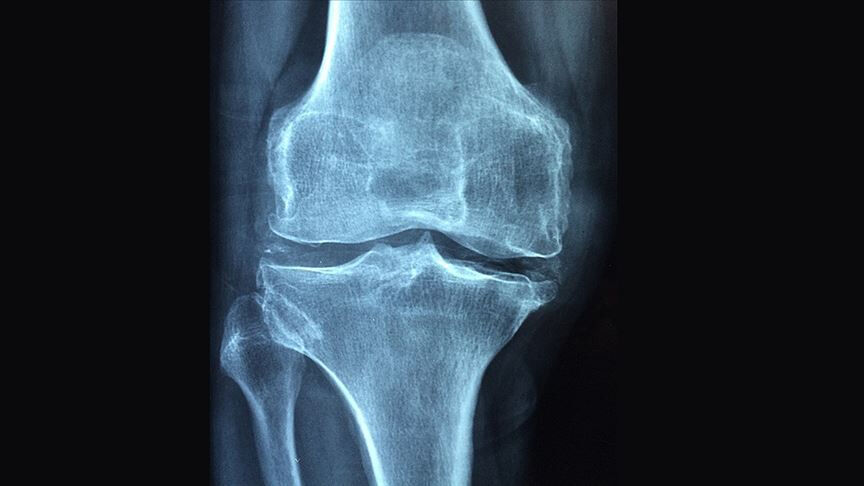

Osteoartrit, artritin en yaygın türü olup yalnızca ABD’de 32 milyondan fazla yetişkini etkiliyor. Kemik uçlarını kaplayan kıkırdağın zamanla aşınmasıyla oluşan bu durum; ağrı, sertlik ve günlük işlevlerde azalmayla kendini gösteriyor. Mevcut tedaviler hayat tarzı değişikliklerinden ağrı kesicilere, ileri aşamalarda ise eklem protezi cerrahisine kadar uzanıyor.

Düşük doz radyasyon tedavisi, Almanya ve İspanya gibi Avrupa ülkelerinde eklem ağrılarında uzun süredir kullanılıyor; ancak dünya genelinde yaygın değil. Bunun temel nedenlerinden biri, yeterli sayıda plasebo kontrollü çalışmanın eksikliği ve radyasyonun her zaman yüksek doz içerdiği yönündeki yaygın yanlış kanı.